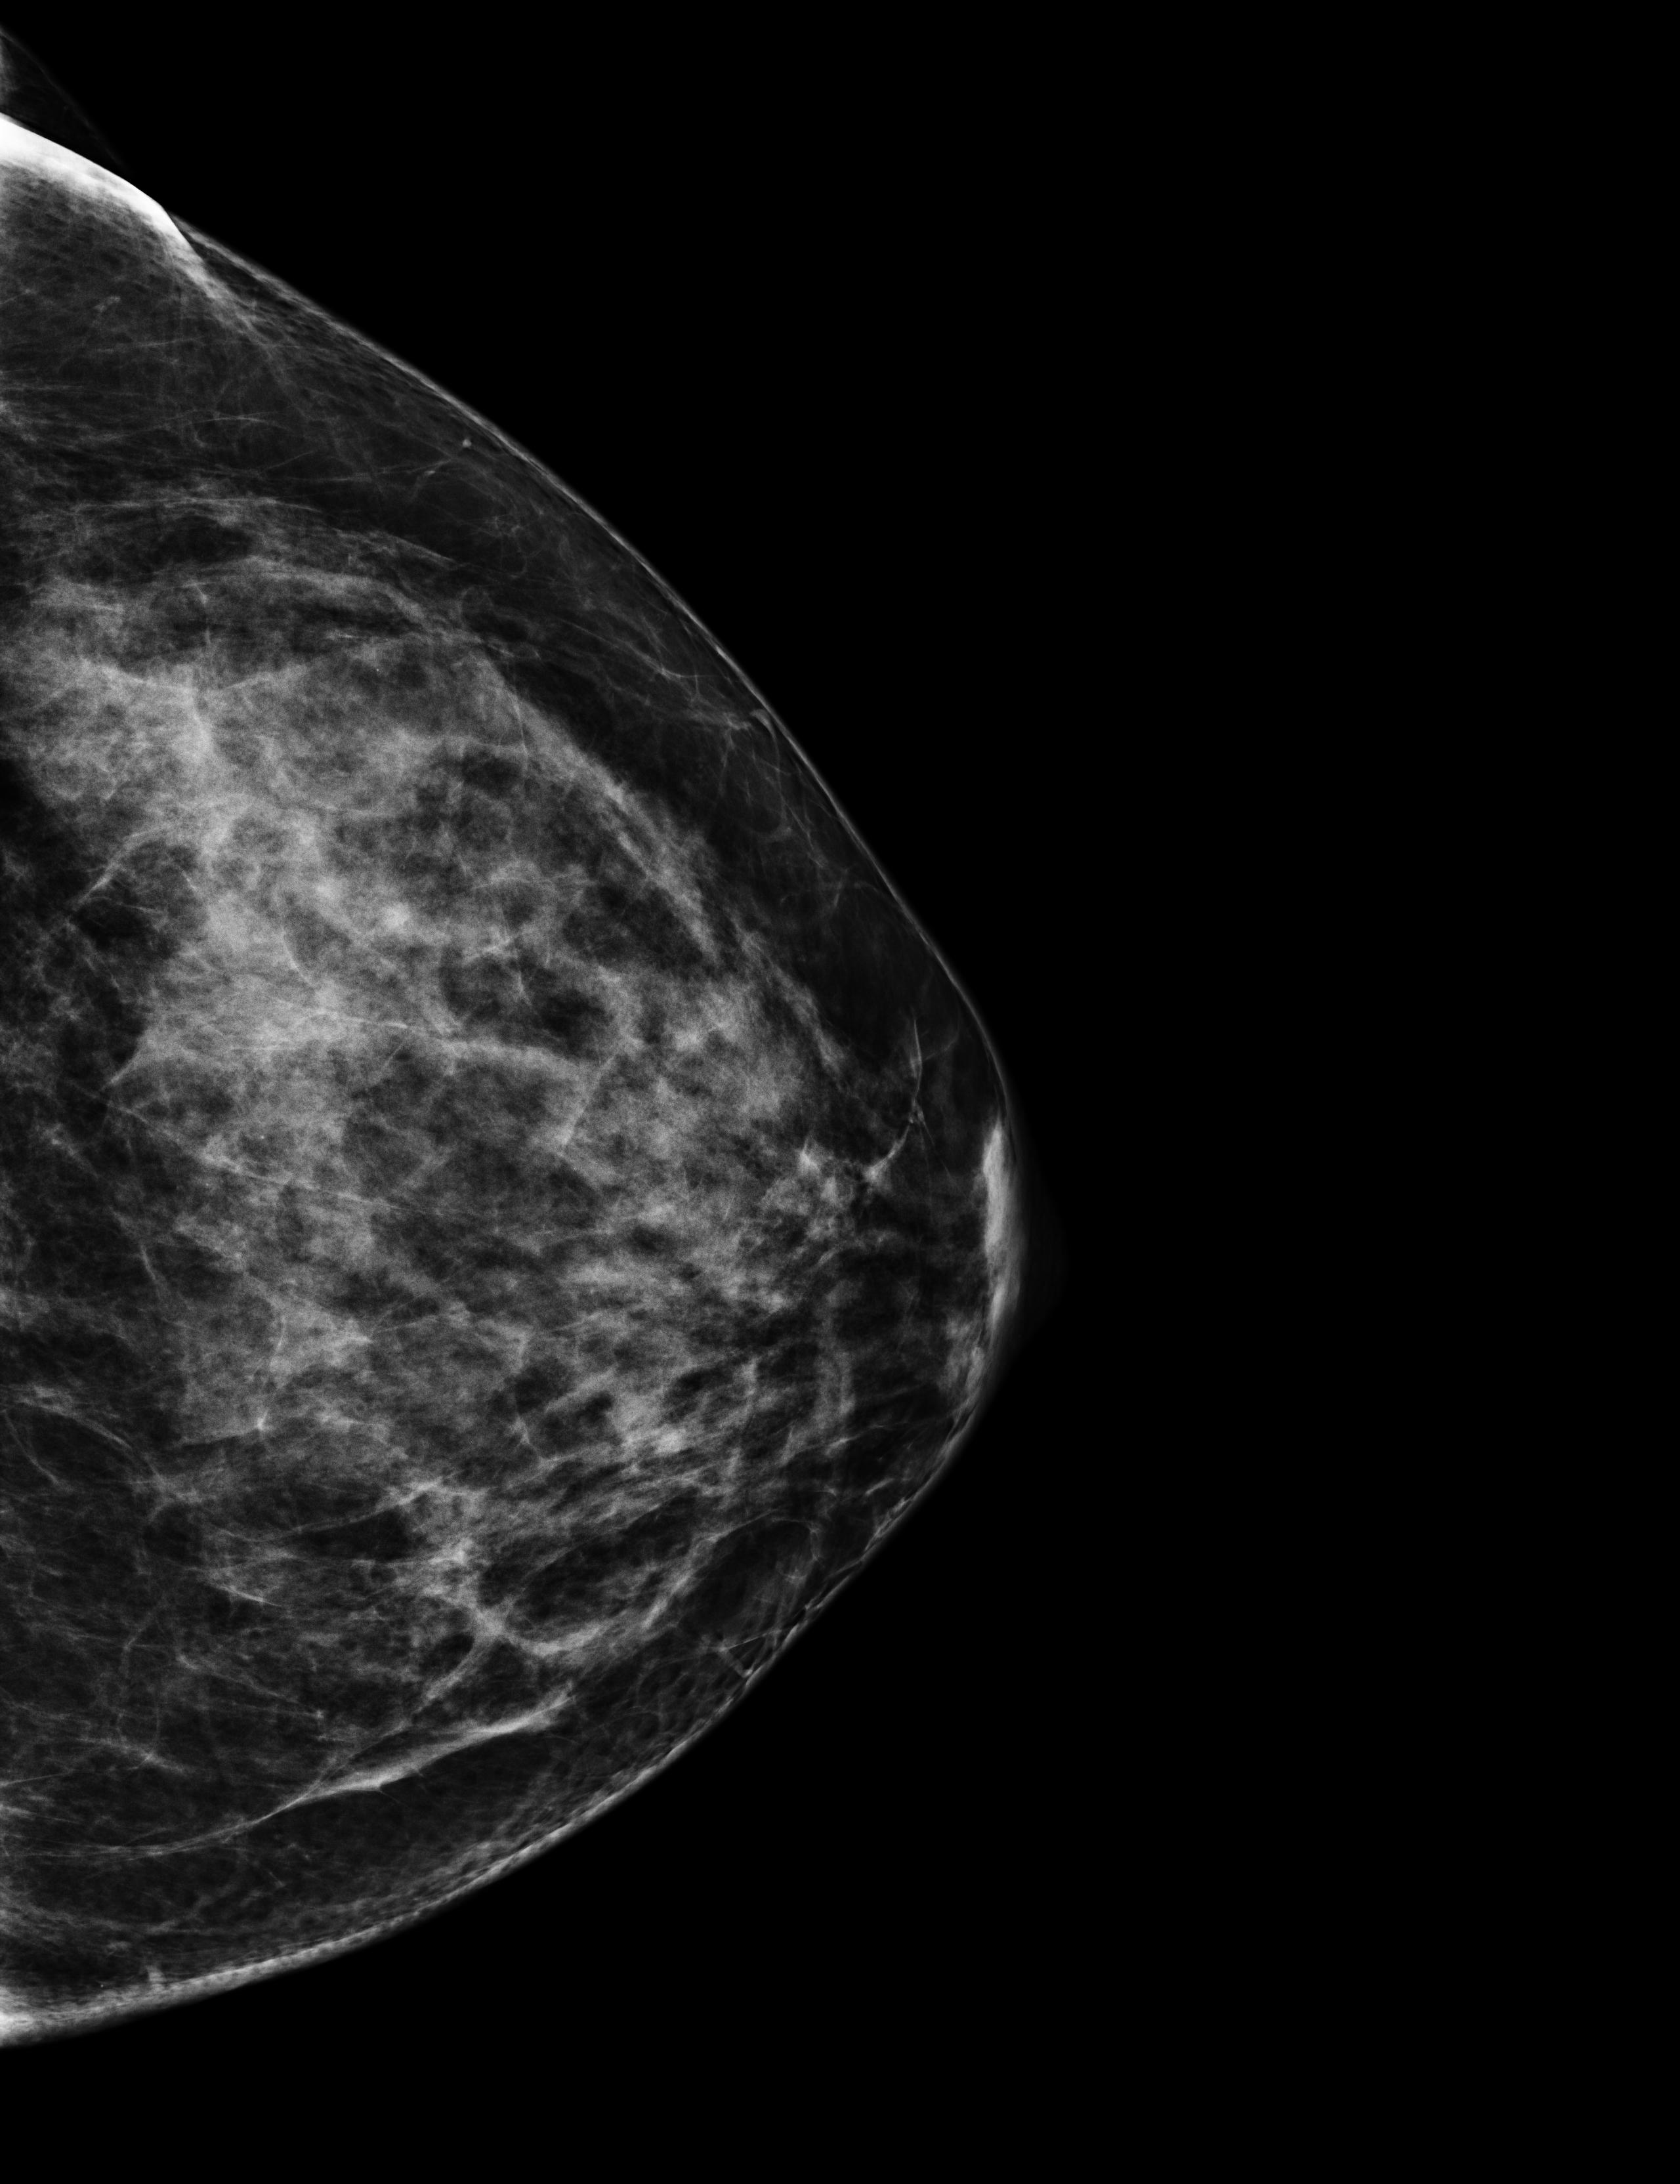

On October 17th 2023 I went to the hospital for an echography; the radiologist asked me almost immediately if they could perform a biopsy. So they stuck a needle in my breast and took out a few tissue samples. It was painful as hell and I ended up crying, confused, and trembling on the bed. The doctor asked me why I went alone for a check of this entity. Well, I didn’t know better, but there was my first lesson:

The data I chose for this day are two scans from the echography, they both clearly show the lesion; the second picture also shows the measurements the radiologist took.